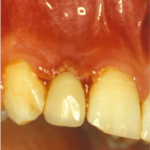

Tracciare il profilo microbiologico di ogni paziente in cura è un atto dovuto nel tentativo di evidenziare le potenzialità patogene di un gruppo di 16 microrganismi imputati nella eziopatogenesi della malattia parodontale o piorrea.

La loro correlazione con la presenza di tasche parodontali, sanguinamento e pus ne fanno degli indiziati speciali se presenti in percentuali elevate.

La sola individuazione, invece, di questi batteri ci permette di agire precocemente e profilatticamente con l’obbiettivo di eradicarne la presenza ed evitare l’insorgenza della malattia parodontale.

Il test microbiologico è quindi nello stesso tempo predittivo di malattia parodontale ma anche indicativo di una possibile evoluzione da patologia borderline a patologia parodontale conclamata.

E non è tutto! Infatti in relazione ai risultati di questi esami emerge una diagnosi parodontale più precisa e conseguentemente possono essere elaborati protocolli terapeutici specifici di grosso impatto terapeutico, migliorando o perfezionando la terapia, sia clinica che farmacologica.